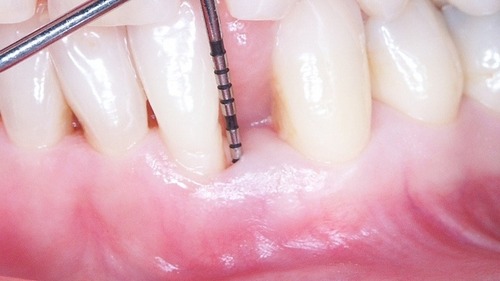

- Extraction avec piezo : Aide à l’extraction / Remodelage osseux

- Travaux pratiques :

Les inserts d’extraction sur mâchoire - Sinus :

- Vidéos tutorielles pour montrer l’utilisation des inserts - Maintenance implantaire

- Protocole de traitement des péri-implantites - Travaux pratiques :